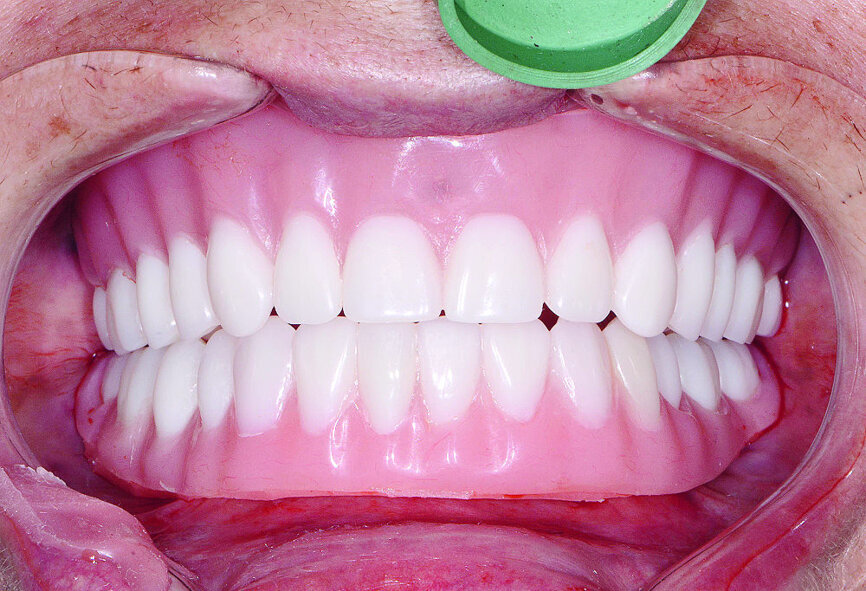

Les restaurations définitives ont été mises en place au cours de la visite suivante et montraient une adaptation, une fonction et une relation inter-occlusale précises (Figs. 21 et 22). Grâce à la phase d’essayage, aucun ajustement des prothèses en zircone monolithique n’a été nécessaire, car les bridges en PMMA avaient permis de définir précisément les modifications nécessaires à l’obtention de la forme et de l’esthétique parfaites. Une dernière radiographie a confirmé l’adaptation totale des restaurations en zircone BruxZir sur les piliers implantaires personnalisés Inclusive. La patiente s’est montrée extrêmement satisfaite de la reconstruction de ses arcades maxillaire et mandibulaire dont le rétablissement de l’esthétique et de la fonction dentaire lui avait rendu confort et confiance.

Fig 21 Vue des dents non engrenées